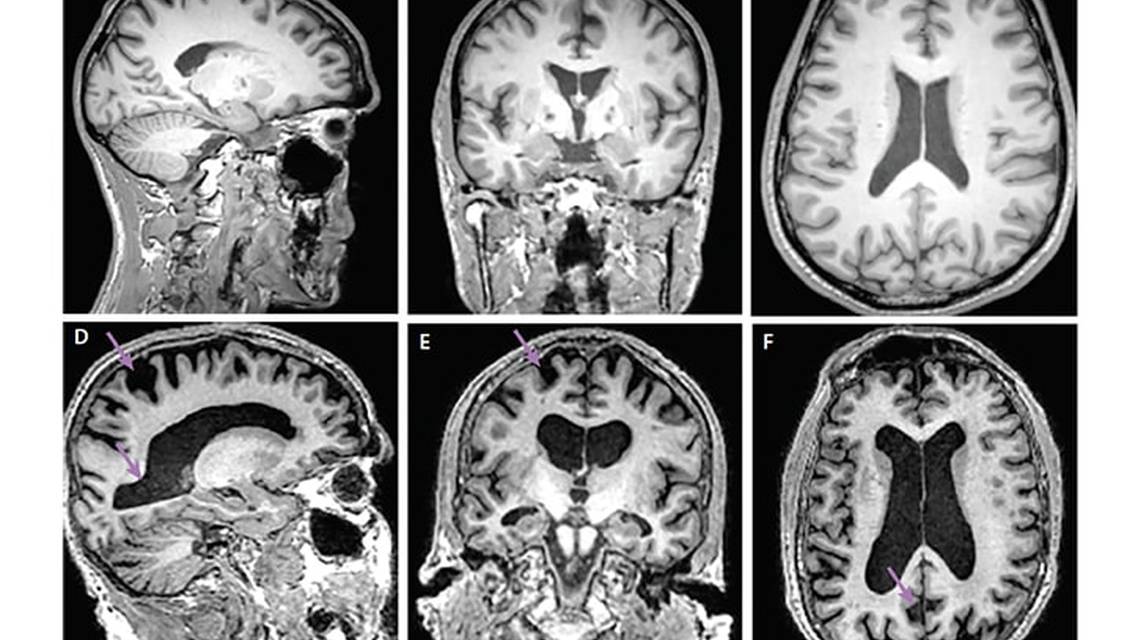

Brain MRI with T1- and T2- weighted sequences can be used for static anatomic evaluation, including relative volume loss, and excluding other anatomic causes of symptomatology (Figures 1 and 2). Characterization of atrophy is still subjective; however, and tends to follow Braak pathologic staging. In MCI and early AD, atrophy is seen primarily in the entorhinal cortex and the hippocampus.5 As AD progresses, atrophy spreads to the rest of the medial temporal lobe (MTL) including the medial temporal, parahippocampal and fusiform gyri, and the temporal pole. Eventually, atrophy progresses to the rest of the cortex, primarily the temporal, parietal, and frontal lobes, although in late-stage AD, the occipital lobe is also affected. As atrophy progresses, the cerebrospinal fluid (CSF) spaces (eg, ventricles, cerebral sulci, and cerebellar folia) enlarge. Rates of ventricle enlargement are higher in AD compared with ventricle dilation typical of normal aging.6 Lateral ventricle size also correlates with AD status and progression.7-10 Atrophy of MTL structures (eg, the hippocampus) correlate well with neuropathology found at autopsy and reliably predicts MCI conversion to AD.11,12

Brain MRI or CT may also help exclude other causes of dementia. In normal pressure hydrocephalus, the ventricles are enlarged out of proportion to volume loss, with crowding of the gyri at the vertices (Figure 2). The use of FLAIR imaging may suggest vascular dementia if white matter disease and lacunar infarcts out of proportion to age are present (Figure 2).